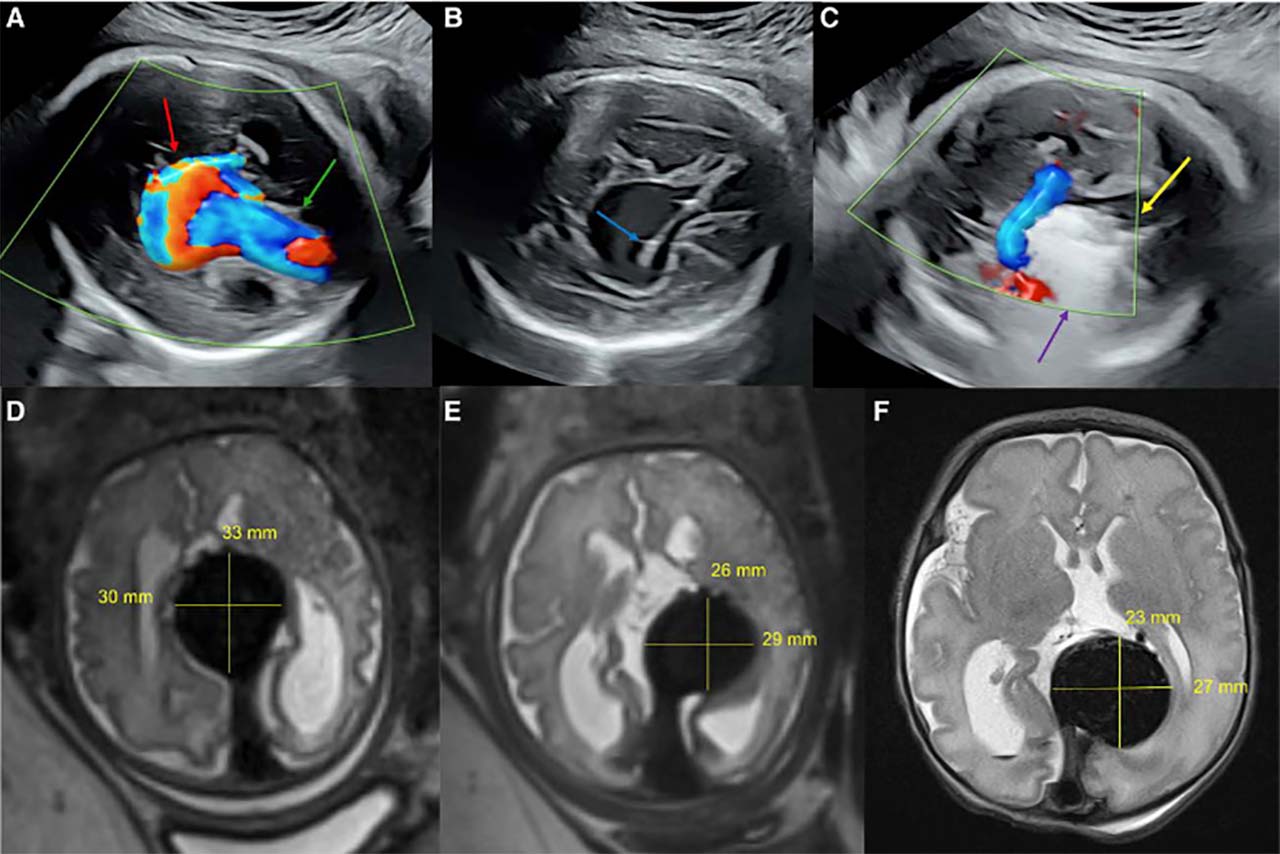

Tıp Tarihinde Bir İlk: Anne Karnındaki Bebeğe Beyin Ameliyatı Yapıldı!

ABD’li cerrahlar, tıp tarihinde bir ilke imza atarak henüz anne...